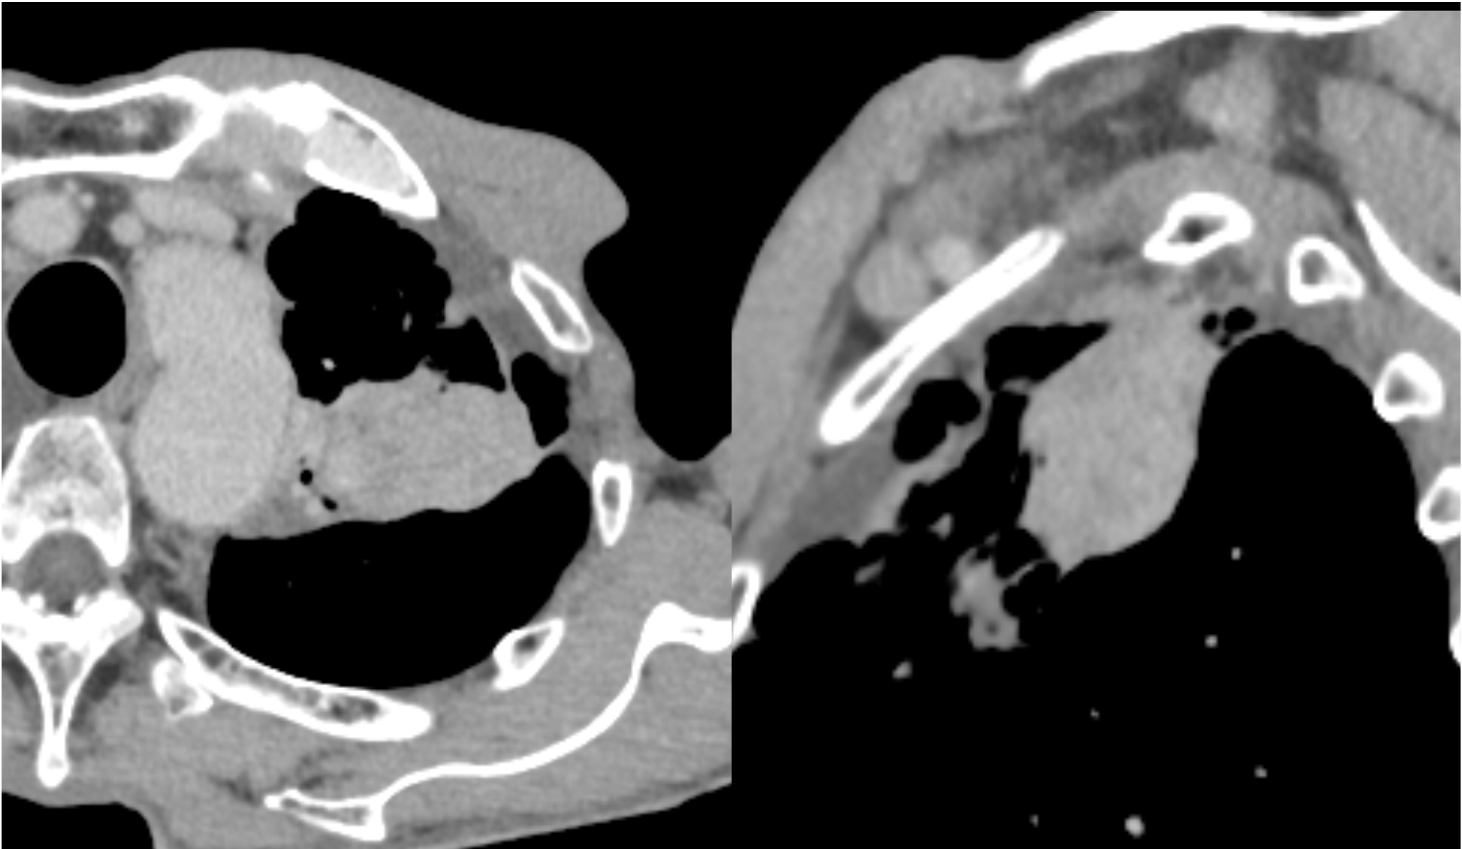

図3.造影CT後期相(Virtual Monoenergetic Image 40keV表示)

40keV表示では、腫瘤の造影効果が図4に比して強調されている。

図4.造影CT後期相(Virtual Monoenergetic Image 70keV表示)

70keV表示は、一般的な後期相の造影効果を表している。